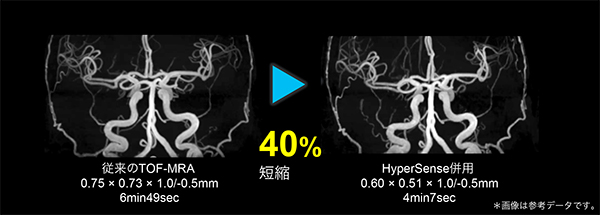

HyperSense(ハイパーセンス)

圧縮センシング技術を応用して少ないデータサンプリングから高分解能画像を再構成することで,スキャン時間を大幅に短縮するアプリケーションです。

従来のパラレルイメージング法は,高い倍速を用いるとアーチファクトやSNRの低下が見られますが,HyperSenseはこれらの影響を受けず,全身領域において短時間で高分解能ボリュームイメージングを提供します。